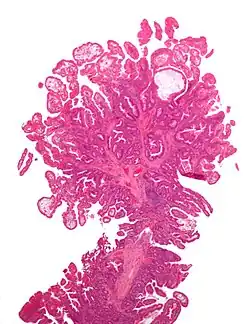

Adenomatous colon polyp with malignant focus at apex

Tubular adenoma 2% at 1.5 cm[12] Low to high grade dysplasia[13] Over 75% of volume has tubular appearance.[14]

Tubulovillous adenoma 20% to 25%[15] 25–75% villous[14]

Villous adenoma 15%[16] to 40%[15] Over 75% villous[14]